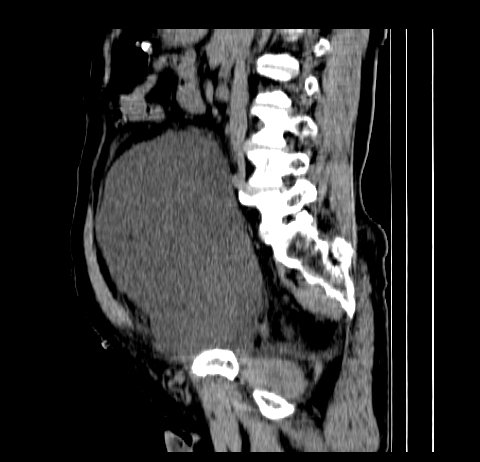

标题: CT19729B:男,74岁,因腿疼就诊,查体触腹部肿物,

增强扫描

动脉期

【临床症状】

分析:

1、老年男性,易患恶性肿瘤;

2、腿痛就诊,一部分恶性肿瘤的患者会分泌一种激素,使凝血机能发生障碍,促下肢静脉血栓形成,致腿痛,有时往往为首发症状。因此,肿瘤不除外恶性肿瘤。

【ct表现】

1、肿块巨大,往往位于腹膜后,长大后才引起症状而就诊;那么位于腹膜后的肿瘤80%为恶性肿瘤。

2、实性肿瘤,增强扫描轻度不均强化,实性肿瘤一般不是好东西。

3、肿瘤边缘似见少许脂肪样密度。

4、腹膜后未见肿大淋巴结,但肿瘤于临近的肠管及组织接触紧密。

【诊断】

腹部占位,考虑位于腹膜后的恶性肿瘤,脂肪肉瘤(实体型)可能性大。

【分析】

1、腹膜后的肿瘤少见,但种类繁多,包括脂肪肉瘤、纤维组织细胞肉瘤、纤维肉瘤、平滑肌肉瘤、恶性畸胎瘤、神经肉瘤、神经母细胞瘤、血管肉瘤及横纹肌肉瘤等,其中脂肪肉瘤为较常见的一种肿瘤。

2、增强扫描强化不明显,除脂肪肉瘤以外,一般肿瘤强化中度以上。脂肪肉瘤可不强化或轻度强化。

术后病理结果:腹膜后脂肪肉瘤。